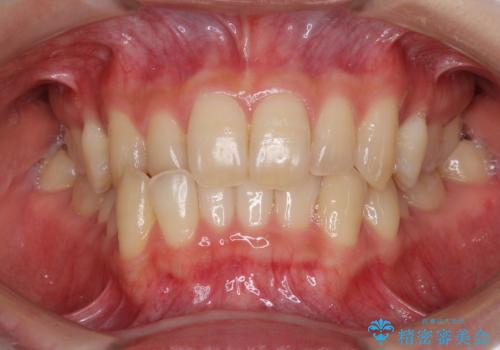

[インビザライン ライト] 短期間(3.5ヶ月)で終わるマウスピース矯正

![[インビザライン ライト] 短期間(3.5ヶ月)で終わるマウスピース矯正の症例 治療前](https://seimitsushinbi.jp/wp/wp-content/uploads/2020/02/C3-500x350.jpg?v=1580813654)